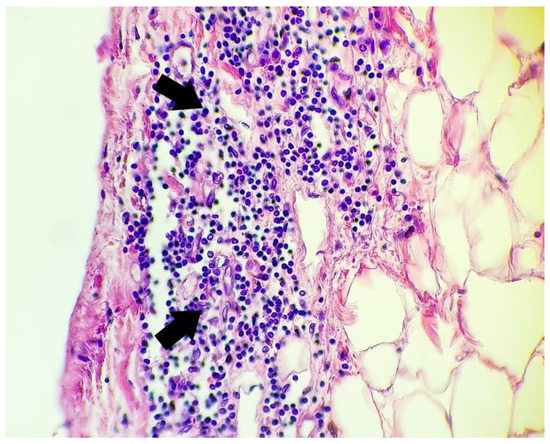

- Lymphocytic inflammatory infiltrate in the subepicardial region and/or visceral pericardium: nine cases

- Marked vascular congestion with large numbers of neutrophils within the vascular lumen: five cases